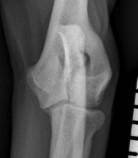

The second theory is that the fissure is a type of stress fracture. Computed tomography (CT) has revealed sclerotic bone being commonly found in the area immediately adjacent to the intracondylar fissure (Figure 1). This bone reaction, typical of a stress-type injury, is consistent with an adaptive biological response to repetitive loading, or a failure of bone repair in an unfavourable mechanical or biological environment. CT has also demonstrated the development of a fissure in a previously normal humeral condyle, as well as the progression of a partial to a complete fissure, suggesting that the lesion is one that develops with time rather than with skeletal development.